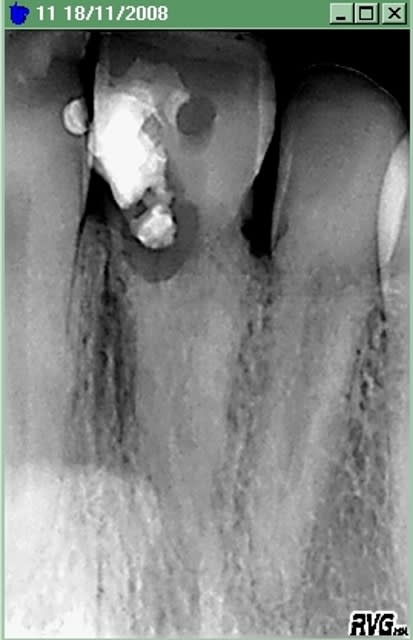

Voila, tout est dans le titre, une patient avec une dent re-implanté suite accident de voiture en 1990. Resorption externe et semble ( comme la 12 ) completement ankylosée.

Vous gerez cela comment ?

Ankylose dldx7r - Eugenol